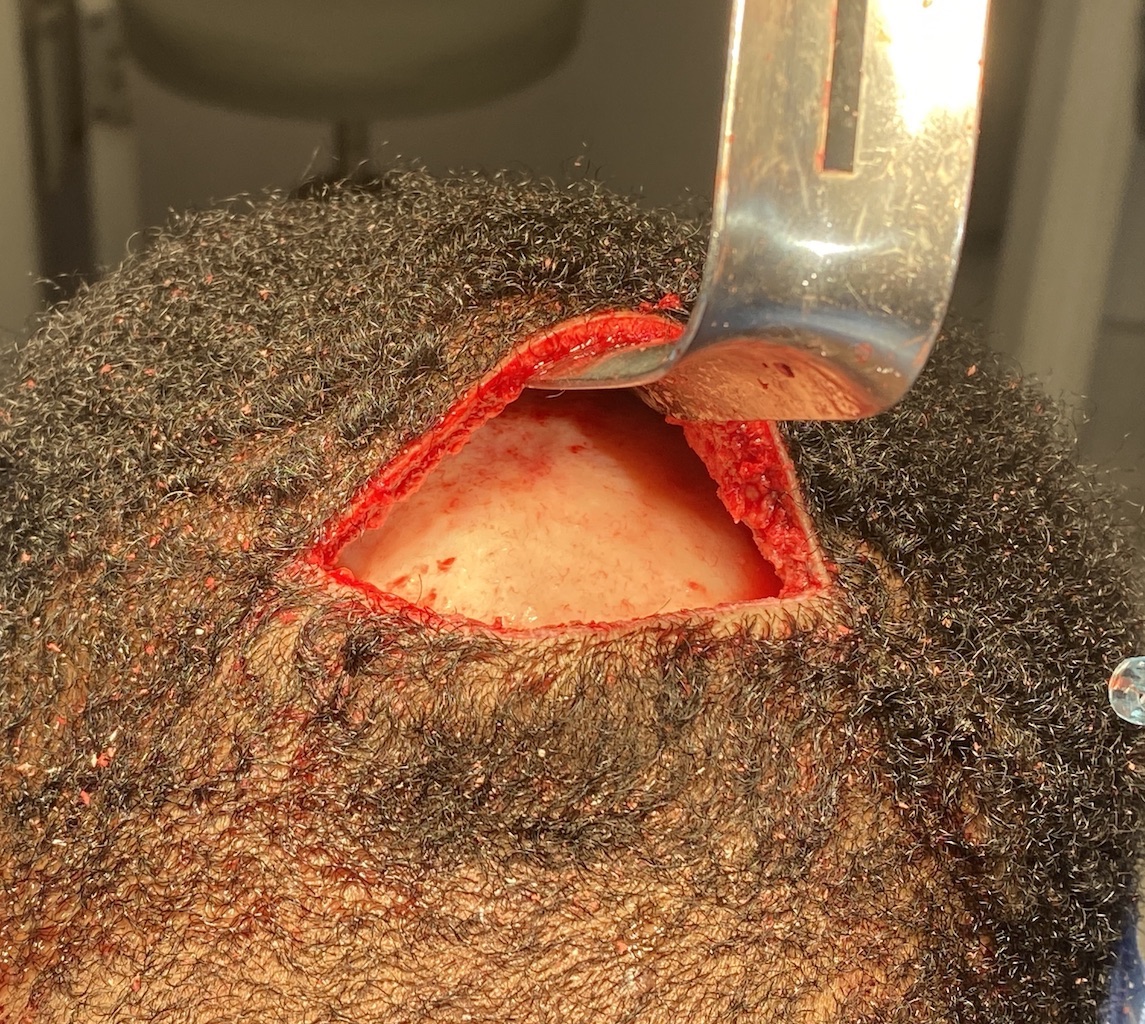

Desire for reduction of prominent occipital knob deformity.

Intraoperative result from occipital knob skull reduction through a direct small scalp incision.

Desire for reduction of prominent occipital knob deformity.

Intraoperative result from occipital knob skull reduction through a direct small scalp incision.